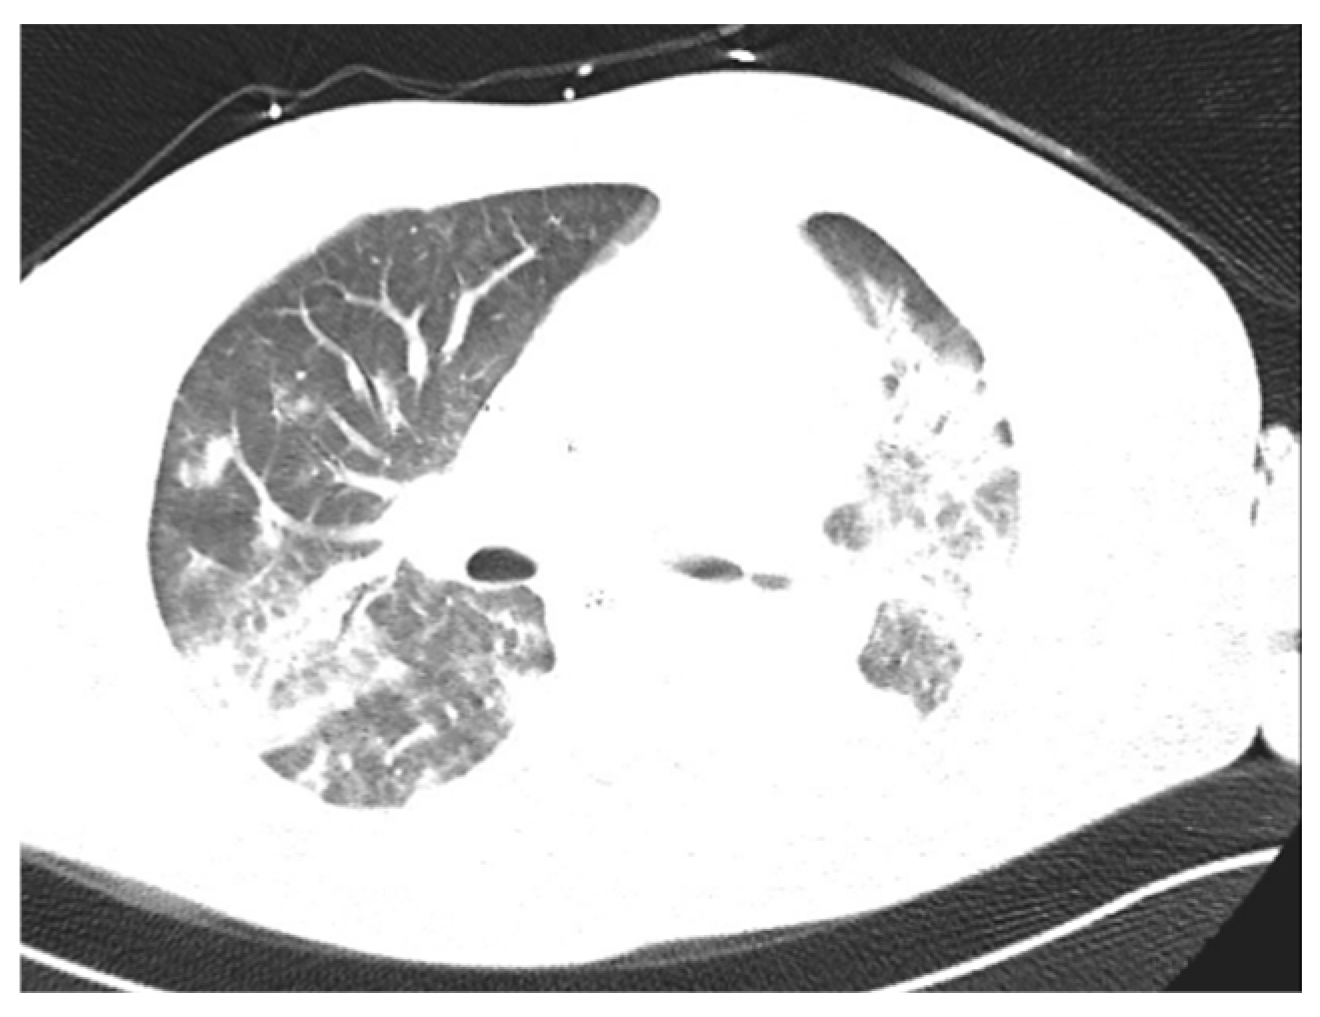

| 6 | 49/F | Pneumonia Pleural empyema | Type 2 Diabetes Mellitus | no | 9 | 3 | no | 58 days | Discharge |

| 6 | No | pleural drainage | pleural fluid | Ceftriaxone Metronidazole | Penicillin Clindamicin |